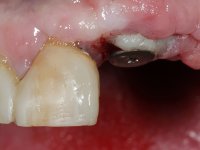

Segunda Fase

6 meses após a colocação da ponte, o paciente sofre um novo traumatismo comprometendo a viabilidade dos dentes 1.2 e 1.1. Foi realizada uma prótese removível acrílica para reabilitar provisoriamente o paciente enquanto foram extraídos os dentes 1.2 e 1.1 e foi colocado o implante no local do dente 1.1. Passados 3 meses foi realizada uma impressão ao implante colocado no 1.1 e simultaneamente foi feito um arrasto da ponte dos dentes 2.1 e 2.2. Para esse efeito no implante 2.1 foi utilizado um parafuso de uma peça de transferência. Dessa forma conseguiu-se impressionar corretamente a arquitetura gengival do sector antero-superior. O objetivo era simultaneamente impressionar corretamente esta zona e aproveitar a estrutura metálica desta ponte para confecionar a nova ponte de 4 elementos. Foi colocado um parafuso de cicatrização no implante 2.1 e foram acrescentados os dentes 2.1 e 2.2 na prótese removível. Com perícia laboratorial foi criada uma nova infraestrutura metálica de 4 elementos assente nos implantes 1.1 e 2.1 e com os elementos pônticos suspensos 1.2 e 2.2. No implante 2.1 manteve-se a conexão interna ao implante no implante 1.1 optou-se por uma peça intermédia facilitando a inserção da infraestrutura. A nova infraestrutura foi verificada em boca. Como pode ter havido alguma alteração da arquitetura gengival com a remoção da ponte e colocação do parafuso de cicatrização no 2.1, foi feita uma chave de silicone para permitir uma impressão de arrasto da infraestrutura metálica. Uma nova gengiva artificial foi realizada no modelo de trabalho de acordo com esta impressão de arrasto. Foi colocada cerâmica de tonalidade coronária e gengival. A peça protética foi aparafusada lentamente em boca para permitir uma adaptação dos tecidos moles. Após o correto assentamento e verificação imagiológica a ponte foi definitivamente apertada em boca e os orifícios de acesso obturados. Independentemente dos infortúnios que o paciente teve, pude ter a satisfação de o ver contente com esta reabilitação.